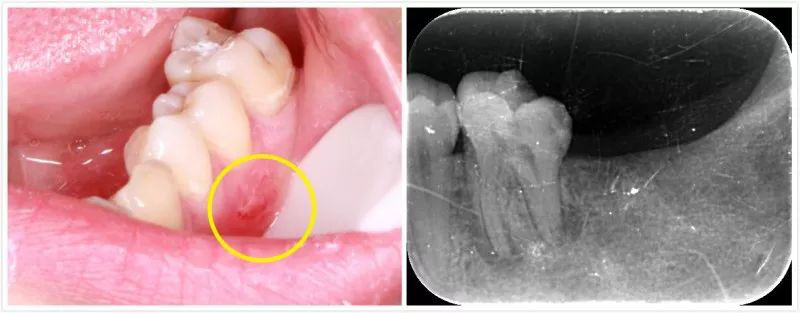

口腔科主任房思炼副主任医师为小野进行了详细的问诊与检查后发现,小野口内左下后牙区仅存一颗大牙,该牙远中区见一大面积树脂样的淡黄色充填物,充填物下方近龈处可探及一深大龋洞,内含大量软腐质。并且在靠近前一颗牙的牙龈处有一个深红色的“脓包”,戳破后见大量脓液从脓包里流出。房思炼使用牙胶尖从脓包处插入,定位瘘管的来源,最后发现病变出处均指向了同一颗大牙。

结合CBCT检查,“痘痘”终于现出了原形!

在CBCT扫描所得的影像中,可以清晰地看到,小野最后一颗大牙的根尖有明确的暗影,所指示的结果为该牙根尖区域已经被炎症所波及,根尖的骨质已经被吸收。

对小野这颗牙行根管治疗术一周后, 从外观上看,侧面可见颊侧瘘管已明显消减,正面也已看不出明显“凸起”。